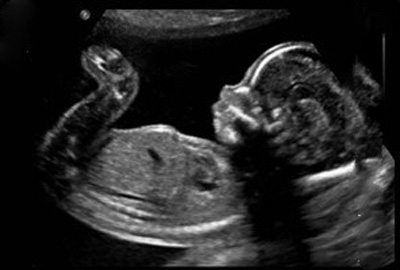

گالری عکس جنین دختر در سونوگرافی به شما اجازه میدهد که ببینید در هفته بارداری جنین پسر چه شکلی است. هر هفته از بارداری می تواند با هفته دیگر متفاوت خواهد بود. این تفاوت ها ناشی از تغییرات وزن مادر، موقعیت قرار گرفتن جنین در شکم مادر و نحوه انجام سونوگرافی که شما بهتر است با تصاویر هر هفته آشنا شوید.

عکس جنین دختر در سونوگرافی هفته هفدهم بارداری